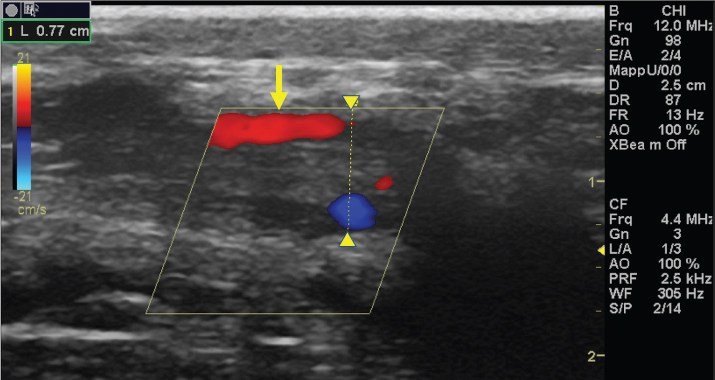

The left jugular vein appeared as an anechoic tubular structure which collapsed under the probe pressure, the color Doppler examination revealed normal blood flow within the vessel (Fig. 3). Bi-dimensional ultrasonography of the right jugular vein showed a heterogeneous, non-cavitating, hypoechoic structure occluding a narrowed right jugular vein for about 30 cm of length localized in the proximal and mid-portion of the neck compatible with a thrombus (Fig. 4). The color Doppler examination showed blood flow through the lateral portions of the thrombus in the cranial and mid-portions of the right jugular vein (Fig. 5). Cranially to the thrombus, a marked distension of the maxillary and linguofacial veins was evident, with a turbulent and echogenic flow; the latter was compatible with blood stasis near the thrombus (Fig. 6). Caudally to the thrombus, the right jugular vein presented reduced diameter, thickened walls, and normal blood flow (Fig. 7). The cranial part of the thrombus originated from a heterogeneous scare tissue, localized at the level of the right mandibular angle (Fig. 8). After injection of the first saline contrast bolus in a right facial vein, no microbubbles appeared in the right jugular vein, caudally to the thrombus, proving the presence of a complete right jugular vein occlusion. On the contrary, after injection of the second bolus, microbubbles were visualized in the left jugular vein as small, intense, echo signals within the vein lumen, demonstrating the presence of collateral circulation that drained the blood from the right facial veins to the left jugular vein (Fig. 9). Venography results confirmed the complete occlusion of the right jugular vein and the presence of submandibular venous collaterals that connected the right facial veins with the left jugular vein (Figs. 10 and 11). Based on the previous results, the diagnosis of JVT with complete occlusion of the vessel lumen was confirmed. The horse’s owner refused any proposed medical or surgical therapy.

Fig. 3. Color Doppler image of the normal blood flow in the left jugular vein.

Fig. 5. Color Doppler examination of the occluded right jugular vein in longitudinal section (between arrowheads). The image shows the presence of blood flow in the periphery of the thrombus (arrow).